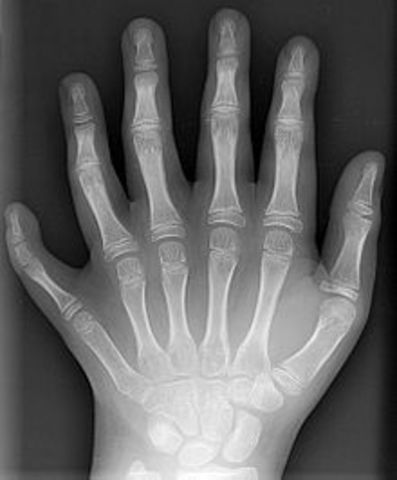

• APARELL DE RAJOS X

APARELL DE RAJOS X

El físic alemany Wilhelm Conrad Röntgen, descobreix un tipus de radiació capaç de travessar els cossos opacs. Com que no savien quina radiació era, la van anomenar "Rajos X".